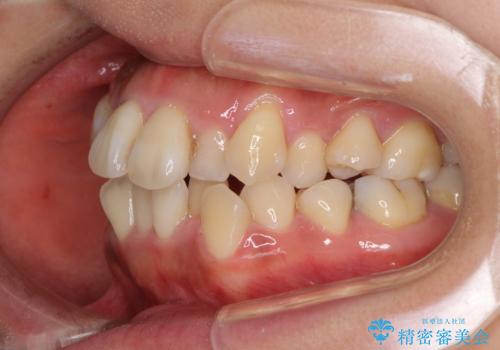

狭い上顎骨を拡大 著しい叢生を抜歯矯正で改善

- 上顎の著しい叢生と奥歯の咬みにくさを気にして来院された患者様です。

骨格的に上顎は狭く、下顎は右側にシフトしていたため、右側臼歯はクロスバイトとなっていました。